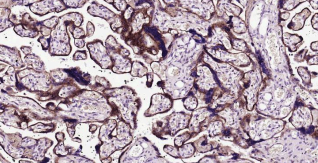

Immunohistochemical analysis of paraffin embedded human placenta tissue slide using IHC0391H (Human LAMP2 Kit).